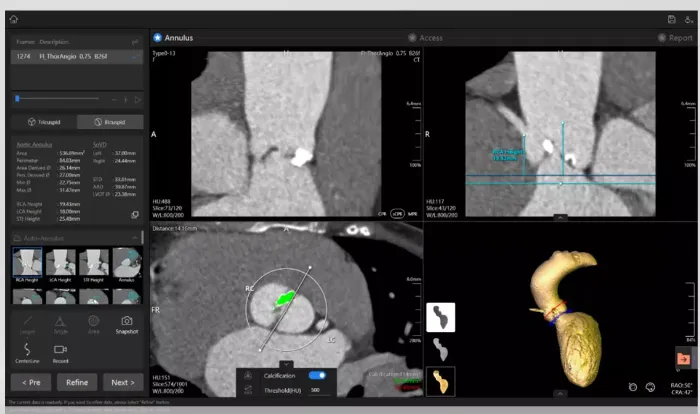

图2:预测仿真模型(DASI Simulation,目前与美敦力合作。可动态预测瓣膜释放后风险,但无法术中实时预测,同类有FEops等)

• 核心产品与功能:核心产品FEops HEARTguide™,是基于云平台的 AI 预测仿真系统,核心能力为:将 CT 影像转化为患者专属心脏数字孪生,模拟经导管瓣膜、左心耳封堵器等植入体与解剖结构的相互作用,精准预测植入后的瓣周漏、器械栓塞、冠脉闭塞等并发症,优化植入体型号选择与着陆区定位。目前覆盖 TAVR、LAAO、TTVR 三大核心术式。

技术优势:全球首个获 FDA/CE 认证的结构心个性化预测仿真平台,临床数据显示可使 LAAO 单器械植入成功率提升 1 倍,瓣周漏发生率降低 60%;

• 核心产品与功能:拥有两款 FDA 认证核心产品:①PrecisionTAVI™:全球唯一拥有 CMS 医保报销代码的 TAVR 个性化预测平台,基于 AI+4D 建模实现术前并发症精准预判,重点聚焦冠脉闭塞、瓣周漏等高风险事件,同时优化瓣膜型号选择;②DASI Dimensions™:拓展至心脏起搏、结构性心脏病其他术式的解剖分析与预测。

技术优势:与克利夫兰诊所联合研发,可精准预测 TAVR 术后血流动力学结果,临床验证可显著降低手术并发症与再干预率;